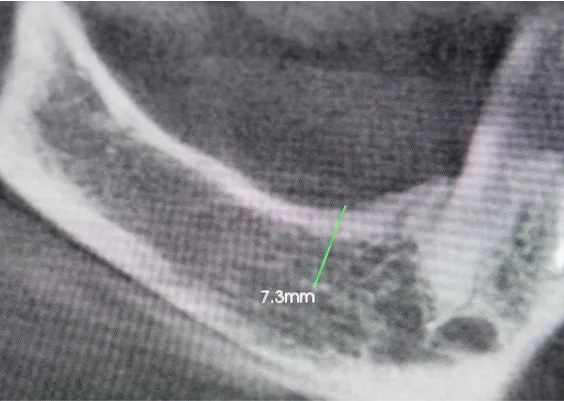

Technika odbudowy kostnej stosowana w celu wszczepienia implantów w zanikłe, boczne odcinki szczęk. Najistotniejszą przyczyną utraty kości wyrostka zębodołowego szczęk w odcinkach bocznych są ekstrakcje zębów. Niedostatek kości w wymiarze pionowym stanowi szczególną anatomiczną przeszkodę dla implantacji w okolicy dna zatoki szczękowej. Chcąc odbudować uzębienie i przywrócić funkcję żucia, trzeba podjąć wieloetapowe leczenie rekonstrukcyjne.

Zabiegiem, który rozwiązuje ten problem, jestpodniesienie dna zatoki szczękowej (sinus lift), czyli odbudowa kostna w okolicy zębów trzonowych. Ubytek kości uzupełniany jest materiałem kościotwórczym, który układany jest pod błoną wyścielającą zatokę szczękową, zwaną membraną Schneidera. Zmniejszając objętość zatoki szczękowej, tworzy się tym samym stabilną strukturę kostną, umożliwiającą zabieg implantacji wszczepów śródkostnych.

Metody operacyjnego podniesienia zatoki szczękowej